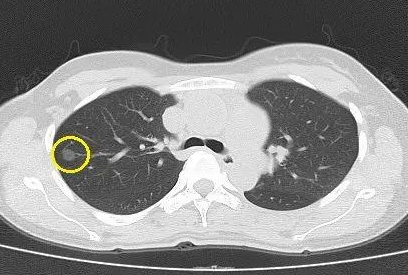

结节形成的原因有很多,有可能是细胞过度增生以后形成的,也有可能与机体炎症以及人的饮食也有关。比如碘摄入过多或者碘摄入不足的时候,可以导致甲状腺出现结节,如结节性甲状腺肿等。肺的结节与吸烟有很大关系,长期的吸烟,刺激性气体伤肺,引起肺内分泌物增多,气管造成炎症,从而引起慢性阻塞性的肺部疾病、青少年哮喘、肺结核等疾病的发生,导致肺结节的形成。也可见于久病、体虚的患者,如长期有慢性支气管炎、支气管哮喘等疾病,也有可能会引起肺结节的形成。所以一旦身体上有结节的时候,建议要及时到医院就医检查,判断结节的良、恶性。